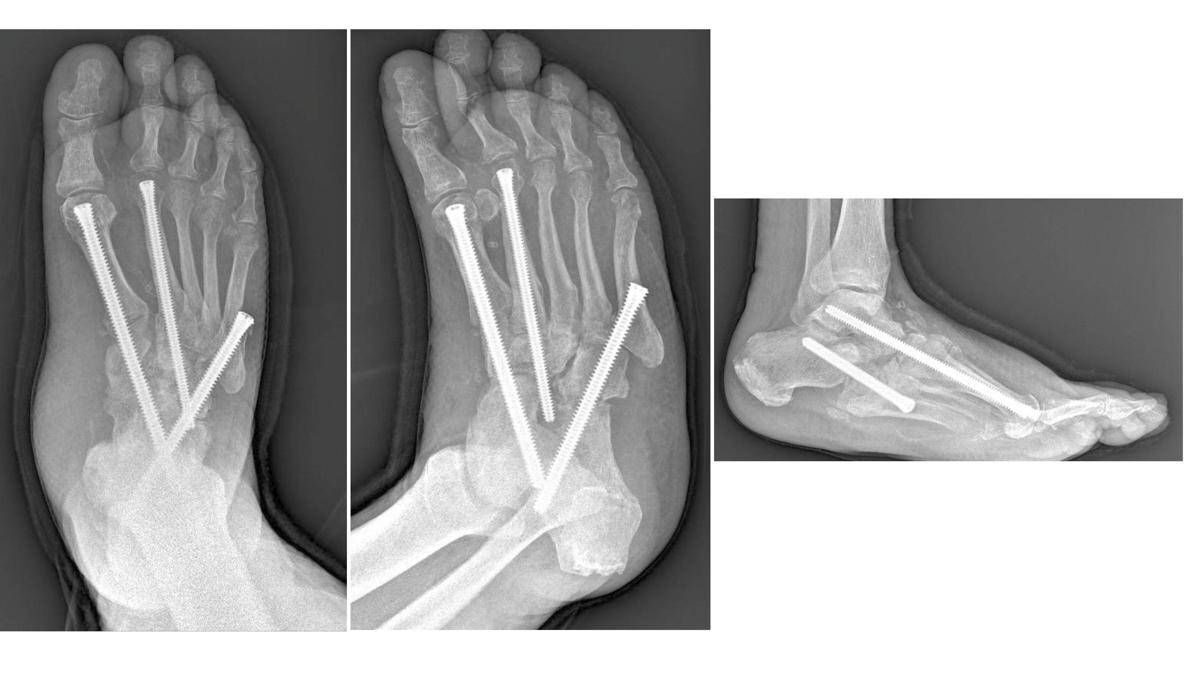

“Nel piede di Charcot – descrive Carlo Perisano, ricercatore in Ortopedia e Traumatologia all’università Cattolica Campus di Roma e dirigente medico presso la Uoc di Ortopedia e Traumatologia del Policlinico Gemelli – assistiamo a una progressiva alterazione dei tessuti molli, delle articolazioni e delle ossa del piede, che vanno incontro a un marcato riassorbimento e a molte microfratture che portano all’instaurarsi delle deformità. Il piede si deforma fino a diventare un ‘piede a dondolo’ (in inglese ‘rocker bottom foot deformity’), a causa della mal consolidazione dell’osso e a una stabilizzazione di quella deformità che determinano una serie di sequele”. Queste, in stadio avanzato, possono essere corrette solo da un complesso intervento, che di fatto diventa una chirurgia di salvataggio dell’arto.

“Sono interventi che mirano a correggere deformità estremamente complesse del piede e della caviglia – illustra Perisano – e che prevedono una serie di procedure chirurgiche (nell’ambito dello stesso intervento), quali osteotomie correttive e successive osteosintesi. Questo consente la ricostruzione di un asse del piede e della caviglia, per permettere al paziente di tornare a camminare (in genere entro un paio di mesi dall’intervento). I pazienti affetti da questa condizione infatti non riescono più a deambulare perché queste deformità comportano alterazioni dell’appoggio, che sottopongono alcune zone del piede, normalmente non deputate a sostenere il carico, ad una pressione eccessiva che a sua volta può portare ad ulcerazioni; queste, nei pazienti diabetici (che spesso sono anche vasculopatici), possono causare infezioni gravi e profonde, che a loro volta comportano un elevato rischio di amputazione”.